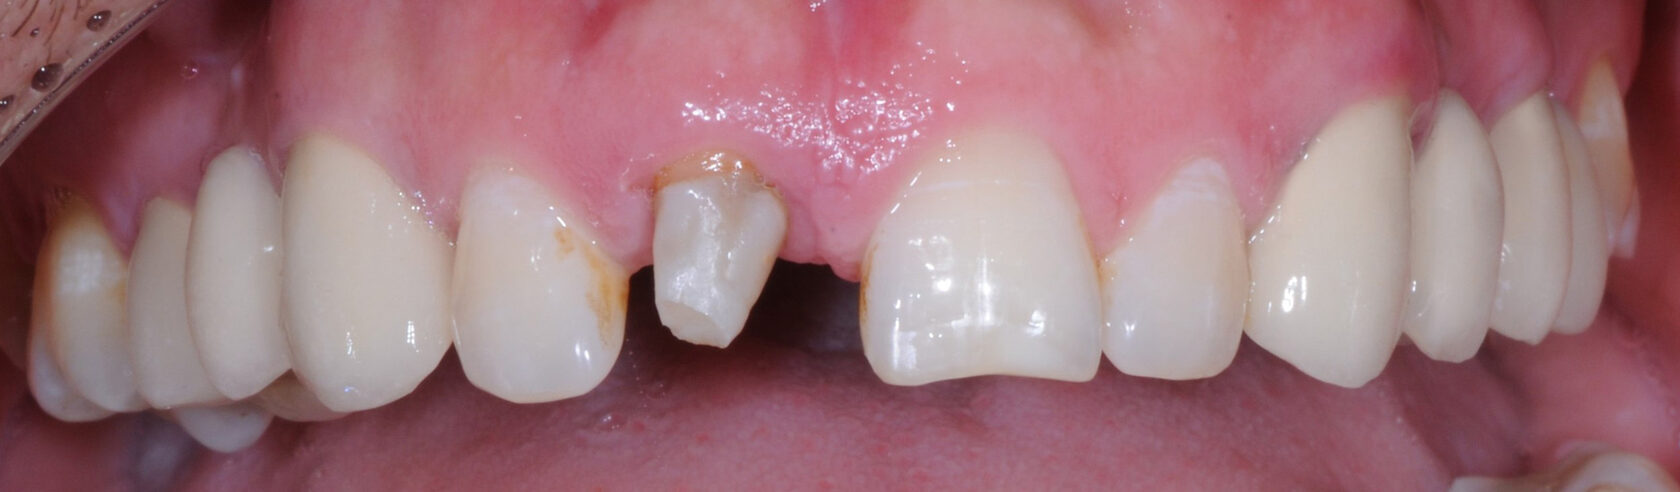

Восстановление резца после травмы с имплантацией Straumann и одномоментным протезированием временной коронкой